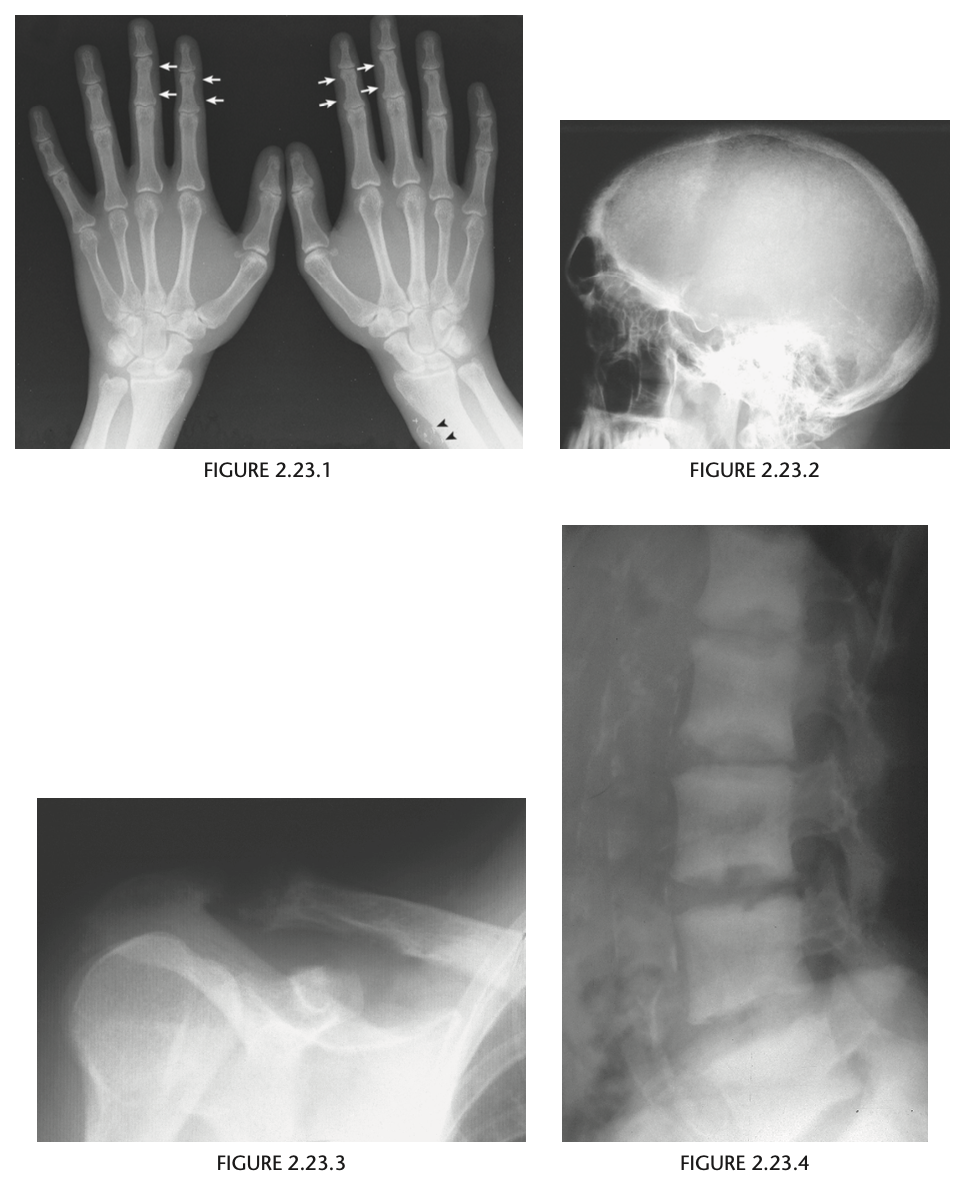

A 23-year-old patient with a chronic disease

Anteroposterior view of the hands of a

patient with chronic renal failure shows subperi-

osteal resorption along the radial aspect of the

middle phalanges of the index and middle fingers

(Fig. 2.23.1, arrows). There are vascular clips from

a graft at the radial aspect of the right wrist (arrow-

heads). A lateral view of the skull in the same patient

(Fig. 2.23.2) shows a salt-and-pepper appearance.

Secondary hyperparathyroidism (HPT)

HPT is a general term referring to an

increased serum level of parathyroid hormone. Pri-

mary HPT results from an intrinsic abnormality in

the parathyroid gland (e.g., an adenoma, hyperpla-

sia, carcinoma). Secondary HPT is caused by a dif-

fuse, adenomatous hyperplasia, and tertiary HPT

develops from an autonomous parathyroid ade-

noma caused by the chronic overstimulation of hy-

perplastic glands in renal insufficiency.

Bone resorption along the radial aspect of

the middle phalanges of the hand (especially of the

second and third digits) is considered diagnostic of

this disorder.

Bone softening may lead to

basilar invagination, wedged vertebrae, bowing of long bones, and slipped capital femoral epiphyses.

Brown tumors, which are lytic, expansile lesions

that may mimic metastases or myeloma, occur in

the jaw, rib, and pelvis and are more commonly

seen in primary HPT. Osteosclerosis, more com-

monly seen in secondary HPT, is characterized by

bandlike sclerosis on the superior and inferior sur-

faces of the vertebral body (i.e., rugger-jersey spine;

Fig. 2.23.4). Soft-­ tissue calcifications can occur in

the viscera, cornea, periarticular regions, and hya-

line or fibrocartilage, causing chondrocalcinosis